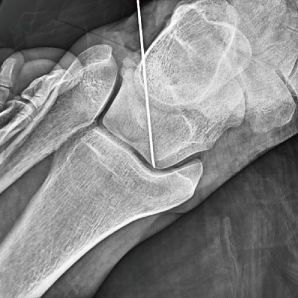

Qualité d'image supérieure avec FPD

Équipé de son détecteur à panneaux plat de 21 * 21 cm ou 30 * 30 cm, ce système produit des images claires et délicates tout en maintenant une large gamme dynamique, offrant une grande visualisation des détails avec un grand champ de vision.